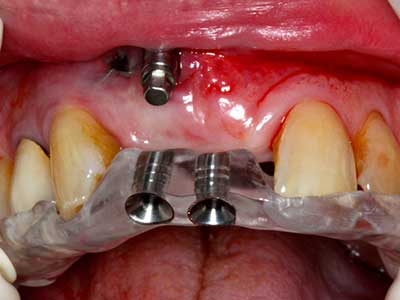

El tejido óseo no solo tiene un contenido puramente mineral, sino que también presenta una importante proporción de fibras de colágeno. Esto no solo garantiza una buena resistencia a la presión, sino también una cierta flexibilidad, que puede aprovecharse para la realización de aumentos. En la plastia de expansión clásica a efectos de una partición ósea, la cresta maxilar atrofiada se divide en su eje longitudinal y, tras alcanzar una profundidad de osteotomía suficiente, se extiende con cuidado (fig. 13-16), en un caso ideal sin desperiostizar de forma visible el maxilar (Brugnami, Caiazzo et al. 2014, Stricker, Fleiner et al. 2014). Los sistemas de tornillos y placas con distancia de expansión creciente han demostrado su eficacia para distanciar entre sí las dos tablas óseas por debajo del umbral de rotura. Por regla general, se requieren anchuras de hueso residual de al menos 3 a 4 mm (Chiapasco, Zaniboni et al. 2006) para garantizar una flexibilidad y una cobertura ósea suficientes de los implantes que van a incorporarse. En caso necesario, una osteotomía de descarga vertical unilateral o bilateral puede mejorar la flexibilidad. Como alternativa a la técnica clásica se ha descrito una combinación con otras técnicas de aumento, sobre todo en la parte bucal.

Con el uso de sierras piezoeléctricas la división se efectúa de forma especialmente cuidadosa y sin pérdidas importantes de las dimensiones, por lo que no se han encontrado diferencias significativas entre los implantes realizados en el maxilar dividido y en la cresta alveolar no deficitaria (Chiapasco, Zaniboni et al. 2006, Danza, Guidi et al. 2009). No obstante, precisamente en la partición profunda y limitada de forma local, es preciso asegurarse de que exista una adecuada irrigación por agua para evitar que se produzcan sobrecargas térmicas en las áreas de osteotomía apical.